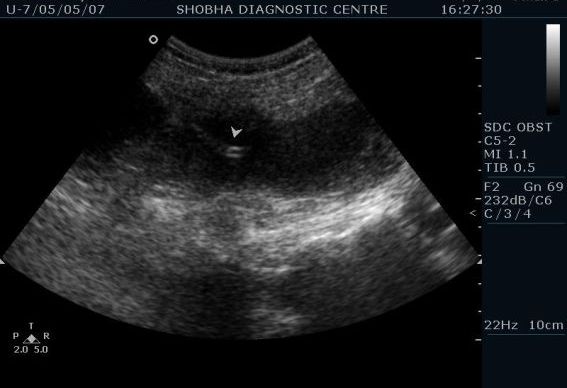

USG guided procedures--- FNAC / Biopsy / Pleural, ascetic fluid Tapping and drainage procedures

Interventional procedures like taking tissue sample from tumor, taking out fluid accumulated in chest wall or abdominal cavity, aspirating pus collected inside the body are safely done under ultrasound guidance where we can see the needle path.